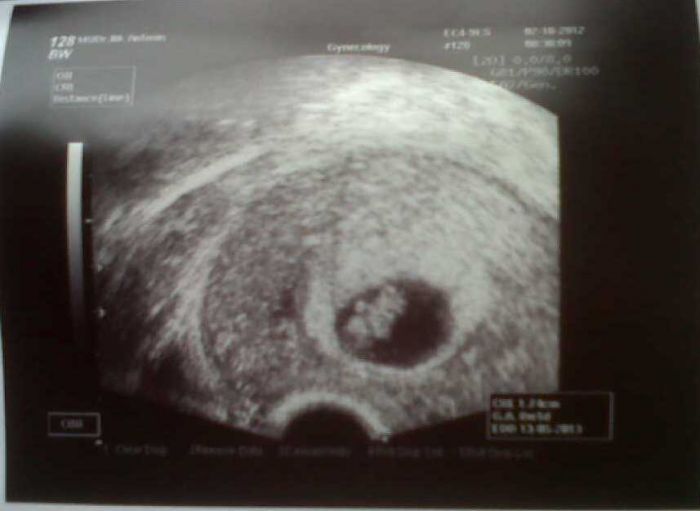

Ještě se pochlubím naším Bobišákem, ať to máte dnes ode mě kompletní. Jinak jsem celé odpoledne prospala, 4 zkumavky krve mi daly zabrat :-)

Ahojky holky,tak jsem se konečně dostala k PC a všechno si to tady pročetla.A prvně bych chtěla pogratulovat zoriazz ke krásné fotečcce.Máš pěknou fazolinku.